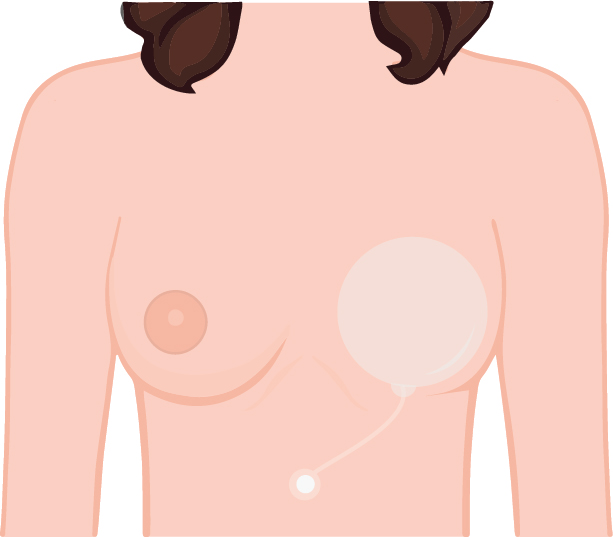

คนที่เป็นมะเร็งเราจะใส่ EXPANDER เพื่อที่จะไปขยายเนื้อเต้านม ที่ถูกฉายแสงและถูกตัดออกไป จะเป็นพังผืดรัดแน่น

ตัวขยายนี้ค่อยๆใส่ลงไป จะมีสายที่ไว้ใช้เติมน้ำเกลือ แพทย์จะนัดผู้ป่วยเพื่อการฉีดขยาย EXPANDER ตัวปุ่มใช้สำหรับฉีดเติมน้ำเกลือผ่านสายที่ติดกับแผ่นจะใช้ฝังไว้ที่ใต้หน้าอกช่วงกลางๆ และมาร์คจุดไว้

และค่อยๆเพิ่มน้ำเกลือตามระยะเวลา ค่อยๆขยายไปเรื่อยๆ ขยายจนเท่ากับขนาดที่เราต้องการ

ประมาณ 2-3 เดือนค่อยเอาออก แล้วค่อยใส่ Silicone เข้าไปแทน

คนที่เป็นมะเร็งมี 2 แบบ บางคนตัดเฉพาะเนื้อ โดยที่หัวนมกับปานนมไม่ได้ตัด แบบนี้เสริมด้วยซิลิโคนขนาดที่เราต้องการก็โอเคแล้ว

อยู่ที่ว่าคนไข้ต้องการขนาดใหญ่แค่ไหน ถ้าต้องการขนาดใหญ่ก็ต้องค่อยๆเพิ่มน้ำเกลือไปเรื่อยๆ บางคนเนื้อไม่แข็งมาก ไม่นานก็ยืดขยายมากแล้วประมาณ 1-2 เดือนก็เสร็จแล้ว บางคนเนื้อแข็งมากและต้องการขนาดใหญ่ก็ต้องเติมประมาณ 6-7 เดือน

เสริมสร้างหน้าอกใหม่หลังจากฉายแสงครบ และเซลส์มะเร็งหมดแล้ว หมอมะเร็งก็จะบอกว่าทำได้ แล้วค่อยทำ

คนที่เป็นมะเร็งเราจะใส่ EXPANDER เพื่อที่จะไปขยายเนื้อเต้านม ที่ถูกฉายแสงและถูกตัดออกไป จะเป็นพังผืดรัดแน่น

ตัวขยายนี้ค่อยๆใส่ลงไป จะมีสายที่ไว้ใช้เติมน้ำเกลือ แพทย์จะนัดผู้ป่วยเพื่อการฉีดขยาย EXPANDER ตัวปุ่มใช้สำหรับฉีดเติมน้ำเกลือผ่านสายที่ติดกับแผ่นจะใช้ฝังไว้ที่ใต้หน้าอกช่วงกลางๆ และมาร์คจุดไว้

และค่อยๆเพิ่มน้ำเกลือตามระยะเวลา ค่อยๆขยายไปเรื่อยๆ ขยายจนเท่ากับขนาดที่เราต้องการ

ประมาณ 2-3 เดือนค่อยเอาออก แล้วค่อยใส่ Silicone เข้าไปแทน

คนที่เป็นมะเร็งมี 2 แบบ บางคนตัดเฉพาะเนื้อ โดยที่หัวนมกับปานนมไม่ได้ตัด แบบนี้เสริมด้วยซิลิโคนขนาดที่เราต้องการก็โอเคแล้ว

แต่บางคนทำเสร็จแล้วต้องรออีก 6 เดือน แล้วค่อยมาแต่งบริเวณปานนมและหัวนม โดยการตัดหนังขึ้นมา หรือเรียกได้ว่า เสริมสร้างหัวนมใหม่ ให้เท่ากับฝังที่ไม่ได้ตัด

อยู่ที่ว่าคนไข้ต้องการขนาดใหญ่แค่ไหน ถ้าต้องการขนาดใหญ่ก็ต้องค่อยๆเพิ่มน้ำเกลือไปเรื่อยๆ บางคนเนื้อไม่แข็งมาก ไม่นานก็ยืดขยายมากแล้วประมาณ 1-2 เดือนก็เสร็จแล้ว บางคนเนื้อแข็งมากและต้องการขนาดใหญ่ก็ต้องเติมประมาณ 6-7 เดือน